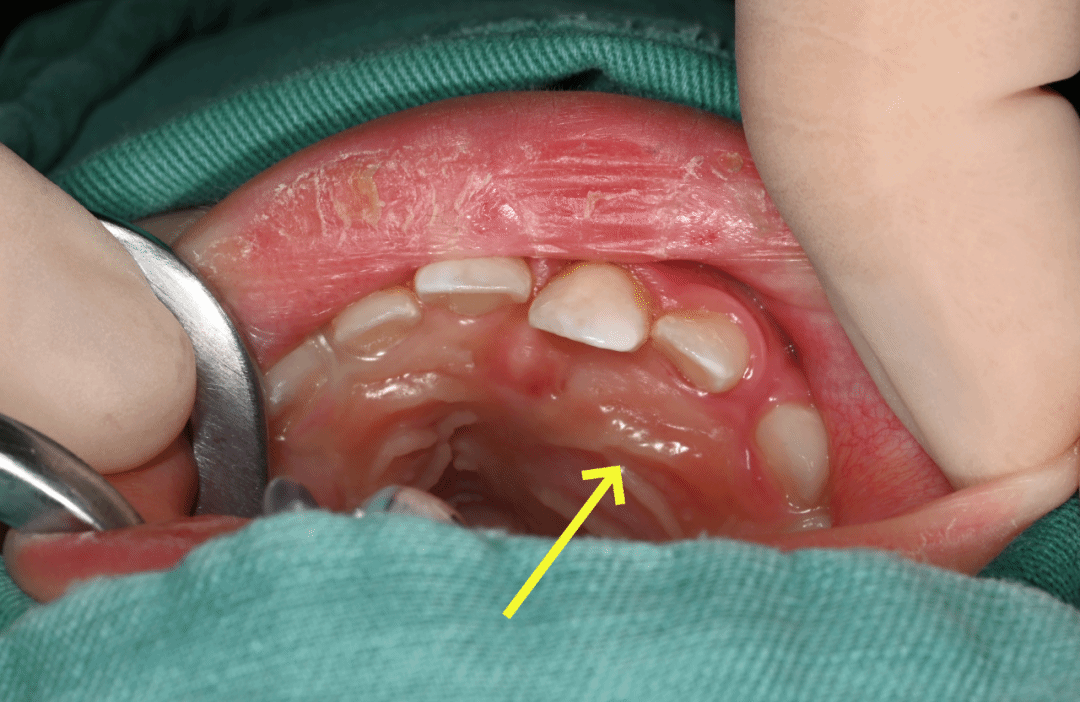

术前小蜻蜓口内照片 黄色箭头指向瘤体

手术历时1小时,在麻醉科的密切配合下,李万山主任通过拔牙创口设计最小的切口,减少创伤,成功完整切除3cmx2cm的假瘤组织,并保留了上颌骨重要解剖结构及连续的颌骨外形,为后续颌骨发育创造条件。